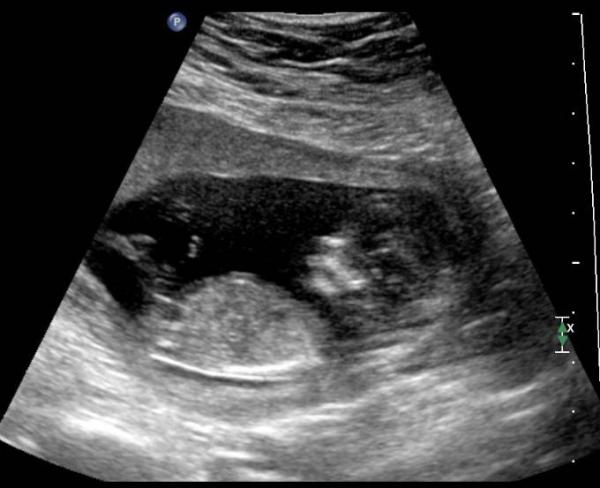

Was für ein Tag ! Nicht nur, dass wir heute in der 14. Ssw gekugelt sind, so hatten wir heute auch einen Termin zur Feindiagnostik. Ich hatte ja schon seit der 5. oder 6. Ssw das Gefühl, dass es ein Junge wird und heute hat sich ein kleiner gesunder Junge offenbart. Es war so schön und so beeindruckend zu sehen, wie viel sich schon wieder getan hat. Meine erste Reaktion, als er den Ultraschallkopf auf den Bauch tat: "Wow, ist es groß geworden". Wenn es nach mir gegangen wäre, hätte ich so gerne noch stundenlang zu geschaut, denn unser Bub war so aktiv (hatte u.a. seine Hand im Mund und sich fleißig bewegt). Der Arzt war wirklich total zufrieden und es gibt keinerlei Anzeichen für eine genetische Erkrankung. Lediglich gibt es bei mir ein erhöhten Risiko für eine Schwangerschaftsvergiftung. Das lasse ich über eine Blutentnahme prüfen, sollte sich das tatsächlich bestätigen, muss ich lediglich nur eine Tablette mehr nehmen (wenn es nur das ist ) Ich bin auf jeden Fall total überwältigt heute und freue mich, dass alles Gut ist < 3

Bild zu erstes Outing - Forum für Juni - Mamis